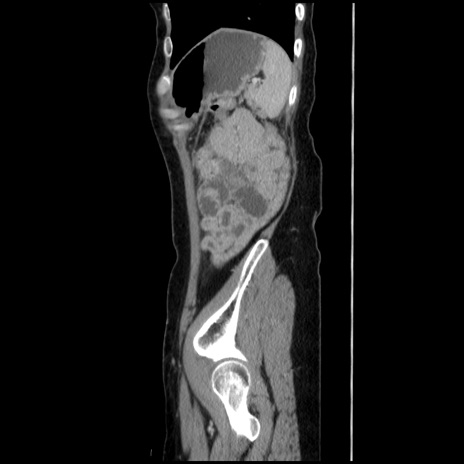

症例32(矢状断像)

【症例】40歳代 女性

【主訴】上腹部痛、嘔気・嘔吐

【現病歴】約9時間前頃から急に上腹部痛、嘔気、嘔吐が出現。改善しないため救急要請。

【既往歴】子宮頚癌(広汎子宮全摘術、放射線療法)、腸閉塞

【身体所見】腹部:平坦、軟、腸雑音亢進、上腹部を中心に腹部全体に圧痛あり。

【データ】WBC 8400、CRP 0.03